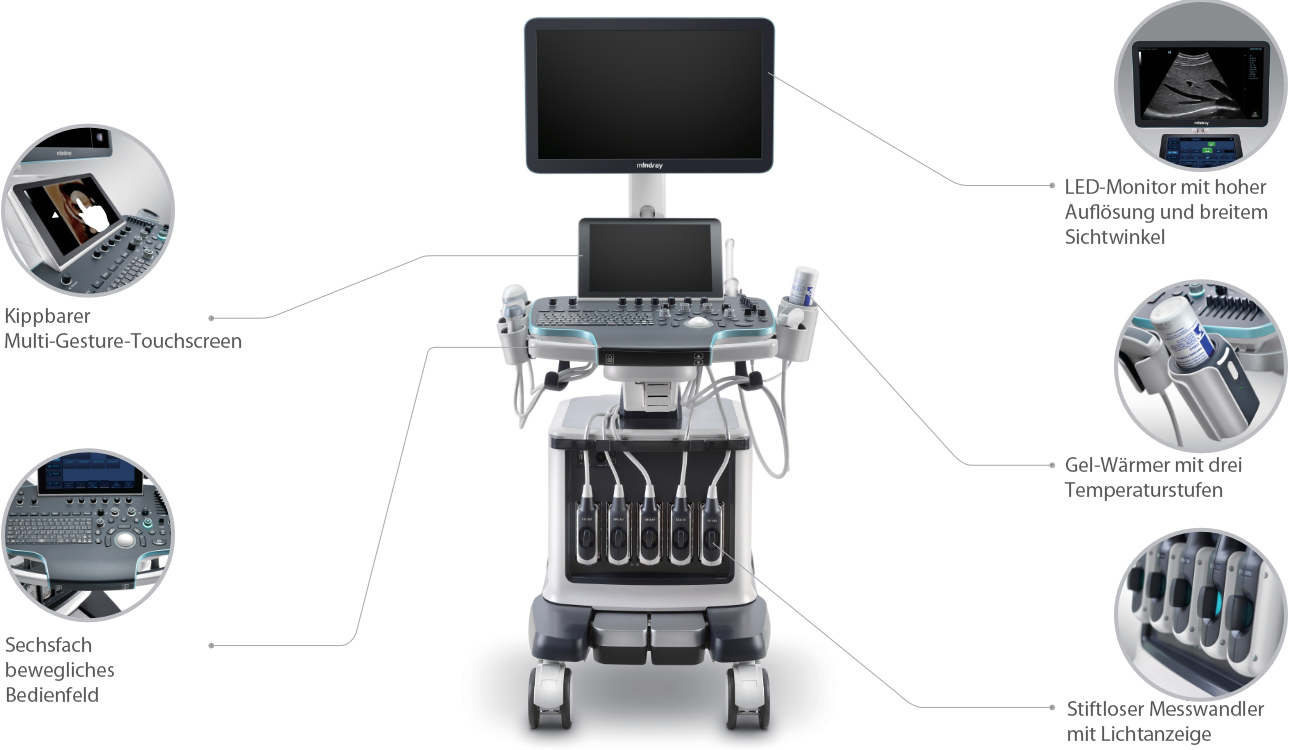

Der hochaufl?sende 21,5 Zoll gro?e LED-Monitor liefert gestochen scharfe Bilder und ideale Rahmenbedingungen. Der in der Neigung verstellbare Touchscreen l?sst sich ganz leicht bedienen und auf die jeweiligen Bedingungen der klinischen Umgebung anpassen.

Von der optimalen Kabelf├╝hrung bis zum Gelw?rmer ist an alle wichtigen Features gedacht worden. Das Resona 7 ├╝berzeugt als modulares Sonographiesystem der Extraklasse. Es bew?hrt sich in der Praxis als ein patientenfreundlicher Begleiter, der mit Liebe zum Detail konzipiert worden ist.